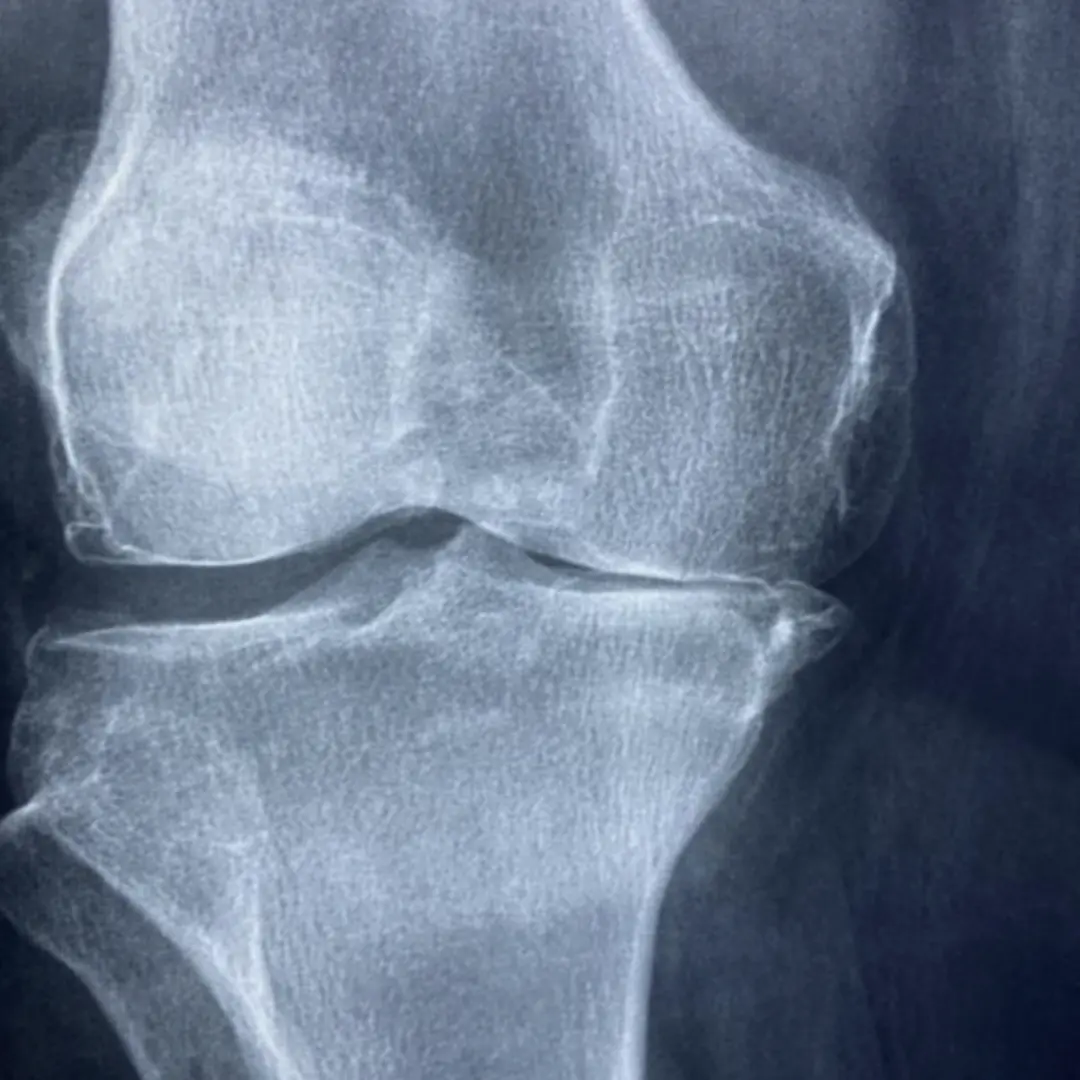

- 가장 흔한 원인 중 하나로, 나이가 들면서 무릎 관절의 연골이 점차 닳아 없어지는 현상입니다. 연골은 뼈의 마찰을 줄여주는 역할을 하는데, 연골이 닳으면 뼈와 뼈가 직접 부딪히면서 통증과 염증을 유발합니다.

- 퇴행성 관절염: 가장 흔한 무릎 통증의 원인입니다. 나이가 들면서 무릎 관절의 연골이 점차 닳아 없어지는 질환으로, 뼈와 뼈가 직접 마찰하면서 통증, 뻣뻣함, 부종 등을 유발합니다. 주로 아침에 뻣뻣하고 움직일 때 통증이 심해지는 특징이 있어요.

- 퇴행성 관절염: 무릎 안쪽 연골이 가장 먼저 닳는 경우가 많아, 관절염 초기에 안쪽 통증이 흔하게 나타납니다.